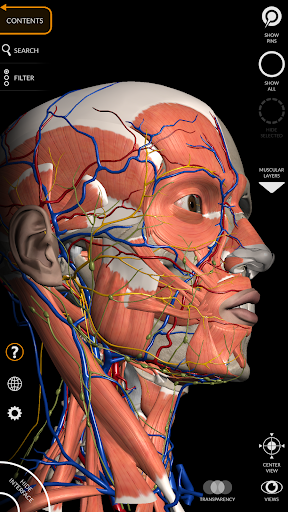

"Anatomy 3D Atlas" дозволяє легко та інтерактивно вивчати анатомію людини.

Завдяки простому та інтуїтивно зрозумілому інтерфейсу можна спостерігати кожну анатомічну структуру під будь-яким кутом.

Анатомічні 3D-моделі особливо деталізовані та мають текстури з роздільною здатністю до 4k.

Поділ за регіонами та попередньо визначені види полегшують спостереження та вивчення окремих частин або груп систем і зв’язків між різними органами.

• Кістково-м’язова система

• Серцево-судинна система

• Нервова система

• Візуалізація м’язів через рівні шарів від поверхневих донизу до найглибших